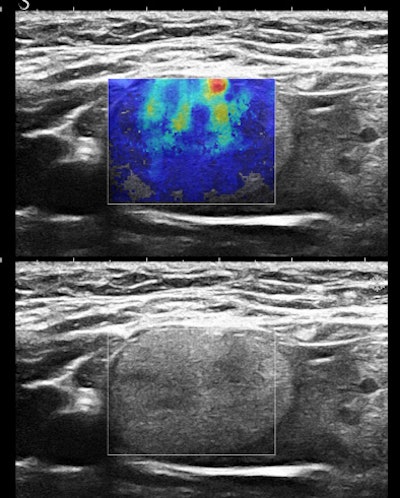

Figures 2A and 2B are cropped B-mode and simultaneous SWE of an 8-mm nodule in an isolated island of parenchyma in the upper outer quadrant of a 43-year-old woman.

![]() |

| Figures 2A and 2B. |

The B-mode features are very abnormal, at the least BI-RADS 4. The elastogram is particularly interesting because the most abnormal area is the halo surrounding the small, peculiarly shaped nodule. This is the desmoplastic border of hard fibrous tissue that the body is erecting to delay tumor expansion. One might infer from this that this tumor has invasive features that are not apparent in the B-mode image. The pathology was microinvasive ductal carcinoma.

The principal determinants of elasticity that are mapped by shear-wave elastography appear to be cell density, interstitial pressure, and fibrosis. Very vascular nodules contribute both increased collagen from vessel walls and interstitial pressure from circulating blood. The important consideration is that these determinants of elasticity are cellular, below the level of resolution of B-mode imaging. SWE would appear to have the potential to reveal some cellular features of tissues.